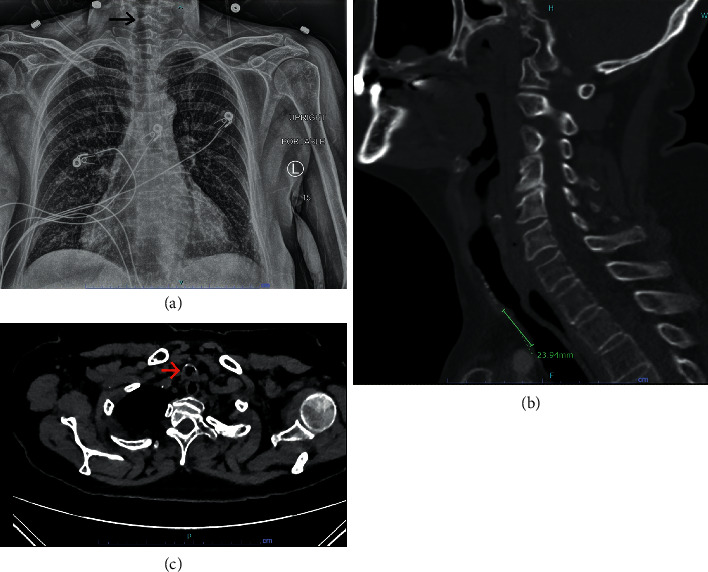

声门下气管狭窄可在长时间插管或气管切开术后发生。这种狭窄可能会变得严重,并导致难以通过内镜干预进行气管切除的症状。由于气道解剖、生理和与外科团队共享气道管理,该手术呈现独特的麻醉问题。我们报告一名68岁的患者,尽管球囊扩张并使用氧气和螺旋手术治疗,但由于症状持续存在,接受了颈椎气管切除术和重建。我们的麻醉管理涉及多种技术,以确保手术安全完成。首先,我们使用4号Ambu®AuraStraight™(丹麦)声门上气道装置和柔性支气管镜进行气道管理,以便在气管内插管(ETT)放置前定位狭窄和扩张。该内镜评估阶段的常规方法是使用刚性支气管镜检查。其次,我们使用先前的CT图像来帮助指导我们选择ETT管的尺寸。第三,我们在大部分手术过程中使用全静脉麻醉,因为完成气管切除术需要间歇性呼吸暂停。最后,拔管必须非常小心地进行,以尽量减少患者过度的颈部运动,避免任何重新插管。这两种情况都可能导致气管重建的灾难。

Subglottic tracheal stenosis can occur after prolonged intubation or tracheostomy. This stenosis can become severe and causes symptoms refractory to endoscopic interventions that require tracheal resection. This surgery presents unique anesthetic issues due to the airway anatomy, physiology, and shared airway management with the surgical team. We present the case of a 68-year-old patient who underwent cervical tracheal resection and reconstruction due to persistent symptoms despite balloon dilation and medical management with oxygen and heliox. Our anesthesia management involved several techniques that allowed the safe completion of this procedure. Firstly, we started the airway management with a combined size 4 Ambu® AuraStraight™ (Denmark) supraglottic airway device and flexible bronchoscopy to allow localization of the stenosis and dilation before endotracheal tube (ETT) placement. The conventional approach for this endoscopic evaluation phase is to use rigid bronchoscopy. Secondly, we used prior CT images to help guide our ETT tube size selection. Thirdly, we used total intravenous anesthesia during most of the procedure because of the intermittent apnea necessary to complete the tracheal resection. Lastly, extubation had to be done very carefully to minimize excessive patient neck movement and avoid any reintubation. Both could lead to a catastrophe with the newly reconstructed trachea.